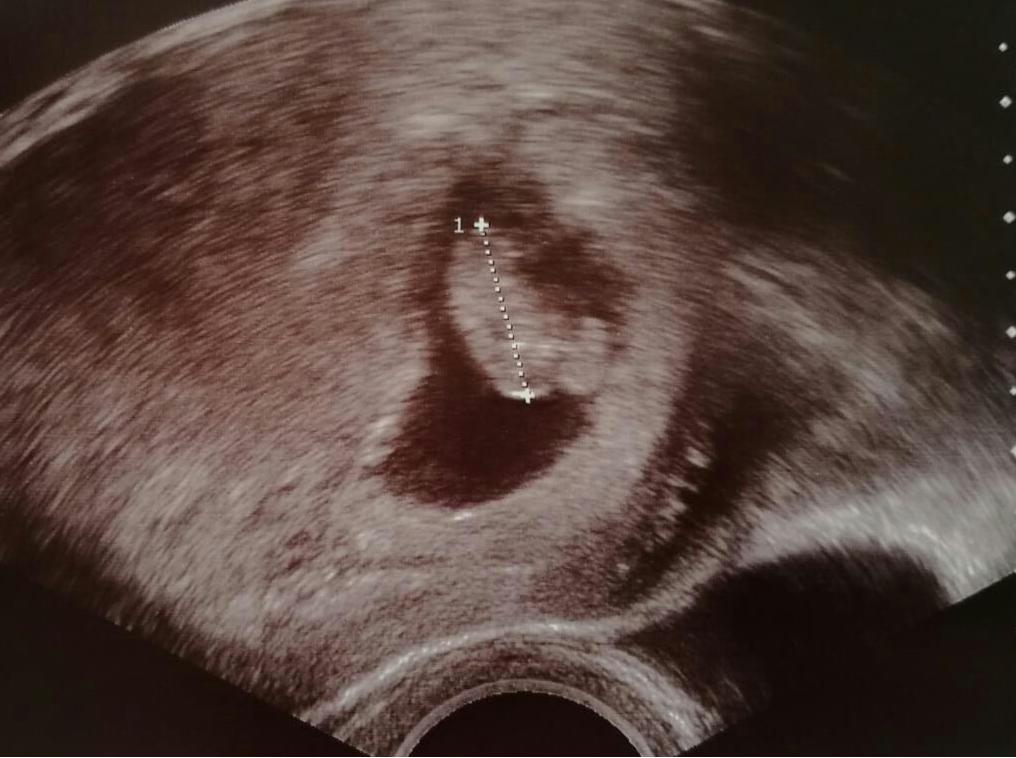

Nur in seltenen Fällen kommt es dazu, dass die Plazenta so dicht am inneren Muttermund liegt, dass es zu Komplikationen kommen kann - der Fachgriff hierfür ist Plazenta praevia. Welche Auswirkungen eine tiefsitzende Plazenta in der Schwangerschaft und für die Geburt hat, erklärt euch unsere Hebamme Katrin Ritter.

Bei manchen Schwangeren liegt die Plazenta an einer schwierigen Stelle. Der Arzt stellt dies im Ultraschall fest. Welche Gefahren dann drohen. Von Beatrice Sobeck , 07.12.2018. Wo liegt die Plazenta? Der Arzt kann das im Ultraschall erkennen. © istock/Natalia Deriabina.

Einteilung bei Placenta praevia